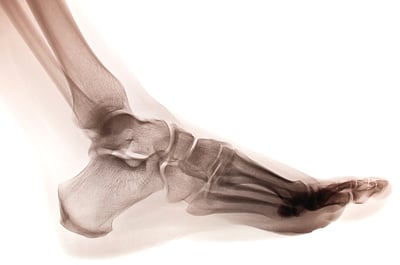

在運動訓練領域中,體能教練常忽略足踝複合體的重要性——若能進行精準分析,此部位將提供關鍵資訊,有助於提升運動表現。

足部本身可視為運動員與地面之間的介面,亦或任何進行運動技能的表面。

評估運動表現時,可從觀察足部與地面之間的力傳遞開始。所有源自這種力交互作用的現象,始終涉及足踝複合體,其功能包含:

- 生物力學補償的終點,以及

- 所有神經肌肉動作的起始點,自下而上貫穿整個前後向動力鏈